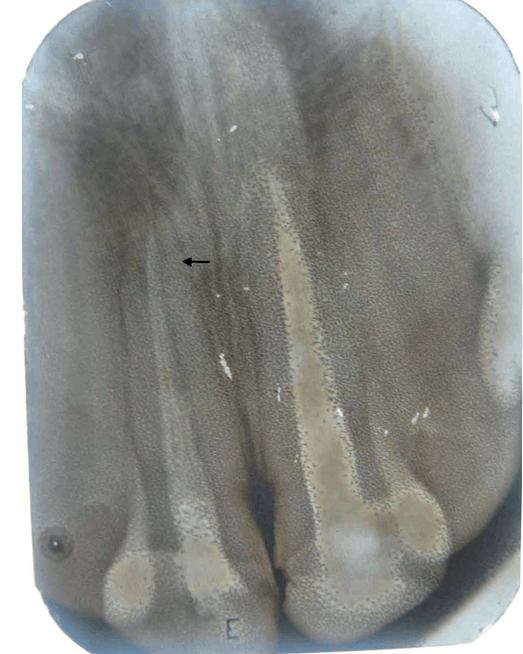

A 14-year-old boy presented to our department with a chief complaint of irregular arrangement of upper and lower teeth. On extraoral examination patient had mesoprosopic, grossly symmetrical face, convex profile with incompetent lips (Figure 1) and (Figure 2). He had a history of trauma to upper anterior teeth at the age of 12 years. On intraoral examination he had Angle's Class-I molar relationship bilaterally with severe crowding in both upper and lower teeth. Both the maxillary central incisors had composite restorations and were severely discolored (Figure 1) (Figure 2). The periapical radiograph showed fractured crowns of both the maxillary central incisors with endodontic treatment of both and a faint fracture line in the apical third of right maxillary incisor (Figure 3). The fracture line was confirmed by taking another periapical radiograph at different tube angle. Although clinically, maxillary central incisors were asymptomatic, but their long-term prognosis was questionable.

Figure 3: Pretreatment intraoral periapical radiograph showing root canal treatment of both maxillary central incisors and fracture line in the apical third of right maxillary central incisor.